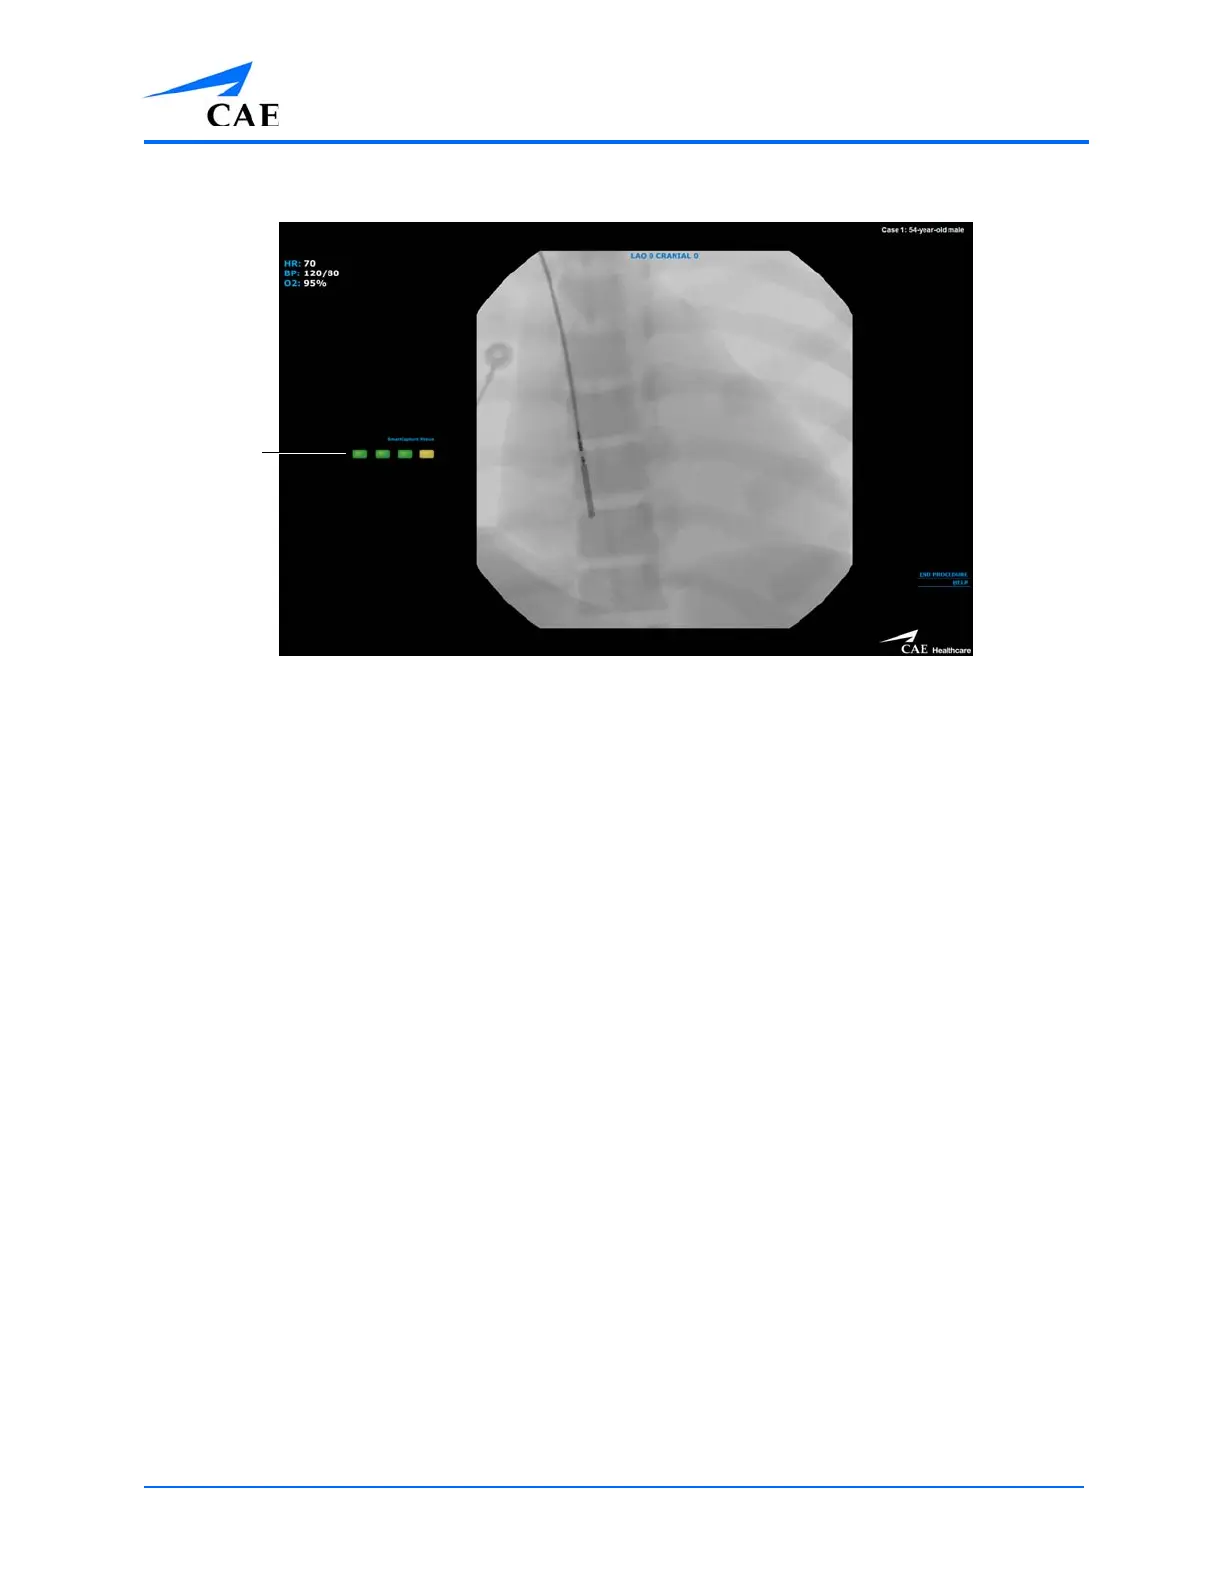

The Simulation Screen

4. Activate the Fluoro feature intermittently to view the path of the tool and navigate

appropriately